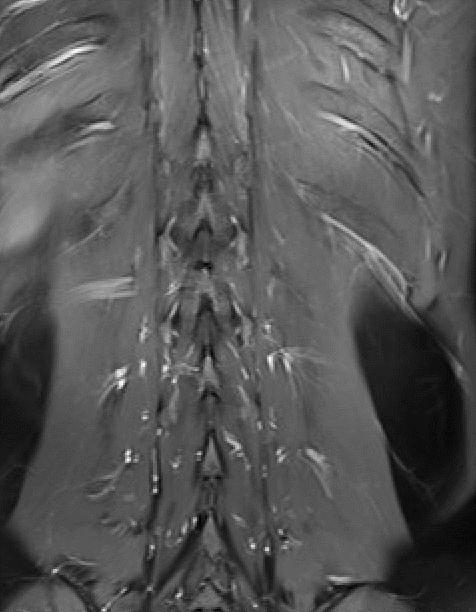

MRI

T1WI矢状位,定位图中所示最下一节为腰5椎体。T2WI、T2WI压脂、T2WI轴位、T1WI增强

C 胸12椎体右侧椎弓根结节状压脂像高信号,增强轻度强化